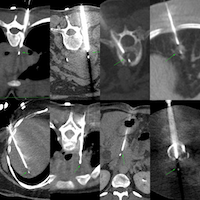

I will be discussing these 7 biopsy cases from Dec 2025, across different levels of difficulty.

The cases were discussed and here is the link to the final video of the livestream.

YouTube Live Session - CT Guided Biopsy Cases from December 2025

7 cases of different levels of difficulty discussed live on 08 Jan 2026